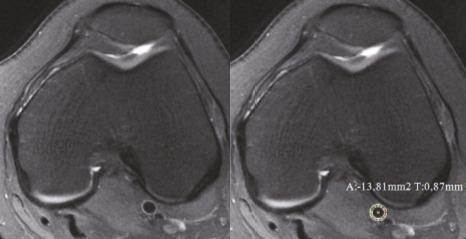

A total of203 patients with different degree of patellar chondromalacia (103 male, 100 female) and 52 control subjects (19 male, 33 female) were included and grouped according to sex, age, body surface area (BSA), body mass index (BMI) and patellar chondromalacia classification. All measurements were completed with 3T magnetic resonance imaging (MRI). Articular cartilage and IFP volume were measured in saggital plane using double echo steady state (DESS) and DIXON sequences, respectively. Patellar cartilage damage was graded using modified outerbridge classification, and the relations among cartilage volume and BMI, BSA, IFP, IMT were statistically assessed.

共纳入 203 例不同程度髌股软骨软化症患者(男 103 例,女 100 例)和 52 例对照组(男 19 例,女 33 例),根据性别、年龄、体表面积(BSA)、体重指数(BMI)和髌股软骨软化症分类进行分组。所有测量均采用 3T 磁共振成像(MRI)完成。关节软骨和 IFP 体积分别采用双回波稳态(DESS)和 DIXON 序列在矢状面测量。髌股软骨损伤采用改良 outerbridge 分级进行分级,并对软骨体积与 BMI、BSA、IFP、IMT 的关系进行统计学评估。